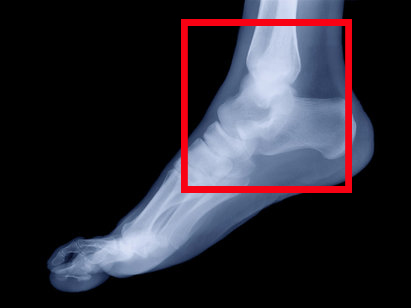

Клинические данные достаточно показательны для того, чтобы поставить правильный диагноз. Но в любом случае, всем пациентам при подозрении на травму голеностопа показана рентгенография голеностопного сустава в двух проекциях. Это мероприятие поможет установить сопутствующие переломы лодыжек и тип вывиха.

Основным методом диагностики вывихов стопы остается рентгенография. Только с помощью рентгена врач-травматолог может поставить точный диагноз (определить тип вывиха) и начать соответствующее лечение. В случае осложненных вывихов с переломами может потребоваться вмешательство хирурга.